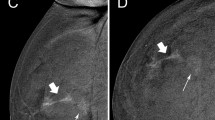

Malignant lesions detected after contrast-directed recall had comparable features to those identified on 2D alone or 2D and C + images in terms of size, grade and nodal status (Table 4). 5/9 (56%) contrast-directed TPs were TNBC or ‘ER-low positive’ (Fig. 2 illustrative case), with two of these patients having ER/PR + HER2- index cancers. Two TPs (2/40, 5%) had no contrast enhancement. One was a small cluster of calcifications with an incidental 1mm invasive lobular carcinoma. The other was clustered calcifications diagnosed as recurrent ipsilateral ER/PR/HER2 + invasive cancer 1 year following BCS and axillary dissection with previous pathological complete response to neoadjuvant systemic therapy. Both patients were on endocrine therapy at the time of recall.

48F Index cancer 2017, 2.8cm TNBC right upper outer quadrant with positive nodes. PET no distant metastases. Treated with NACT with incomplete response. WLE clear margins, 2cm G3 TNBC, 2/29 positive nodes. Adjuvant radiotherapy. 3 surveillance rounds including first CEM 2020, clear. MD BIRADS B. New 19mm NME (white arrow) 2021 anterior to scar, seen on contrast only (2D/3D MG and US normal). MR biopsy 20mm TNBC G3 with LVI. Right Mastectomy